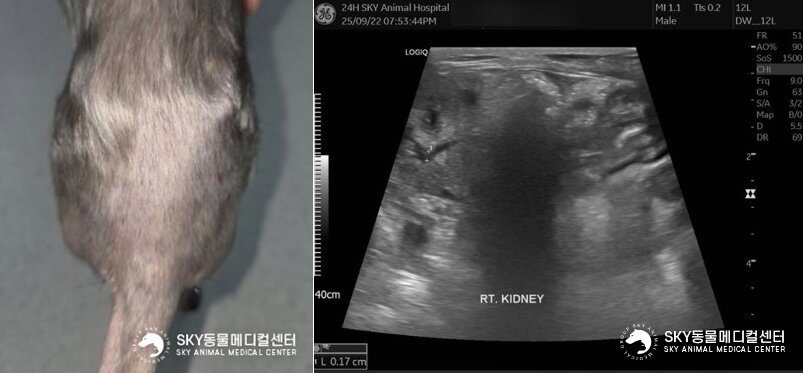

본문 이미지 - 탈장 수술 후 정상적으로 회복된 모습. 초음파 검사 결과 확장된 신우와 요관도 정상 범위 내로 확인됐다(스카이동물메디컬센터 제공). ⓒ 뉴스1

탈장 수술 후 정상적으로 회복된 모습. 초음파 검사 결과 확장된 신우와 요관도 정상 범위 내로 확인됐다(스카이동물메디컬센터 제공). ⓒ 뉴스1